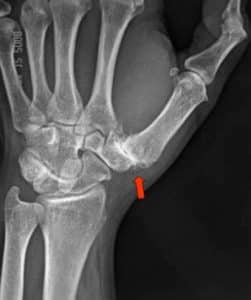

الفصال العظمي شبه المنحرف السنعي (TMC)

المعروف أيضًا باسم داء المفصل الجذري (داء ريز)، هو حالة تنكسية تصيب المفصل عند قاعدة الإبهام، بين عظم شبه المنحرف وعظم مشط اليد الأول. وهو